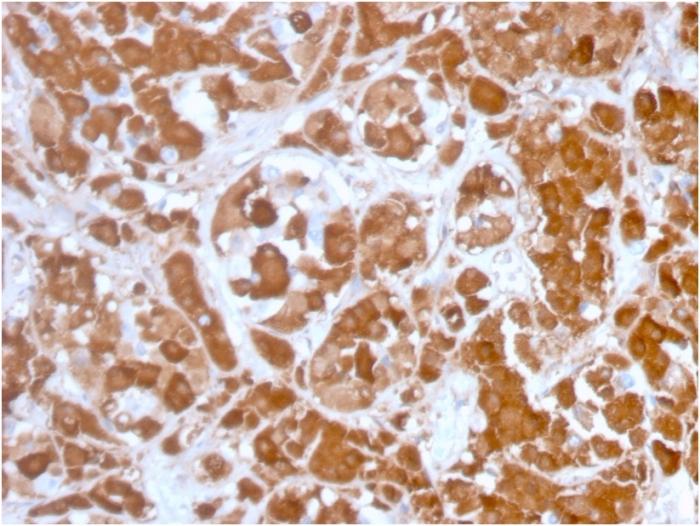

Positive Control

Pituitary cells. Human pituitary tissue (IHC).

Pituitary gland

Pituitary cancer

IHC, FFPE (verified)

IHC (FFPE) (verified)